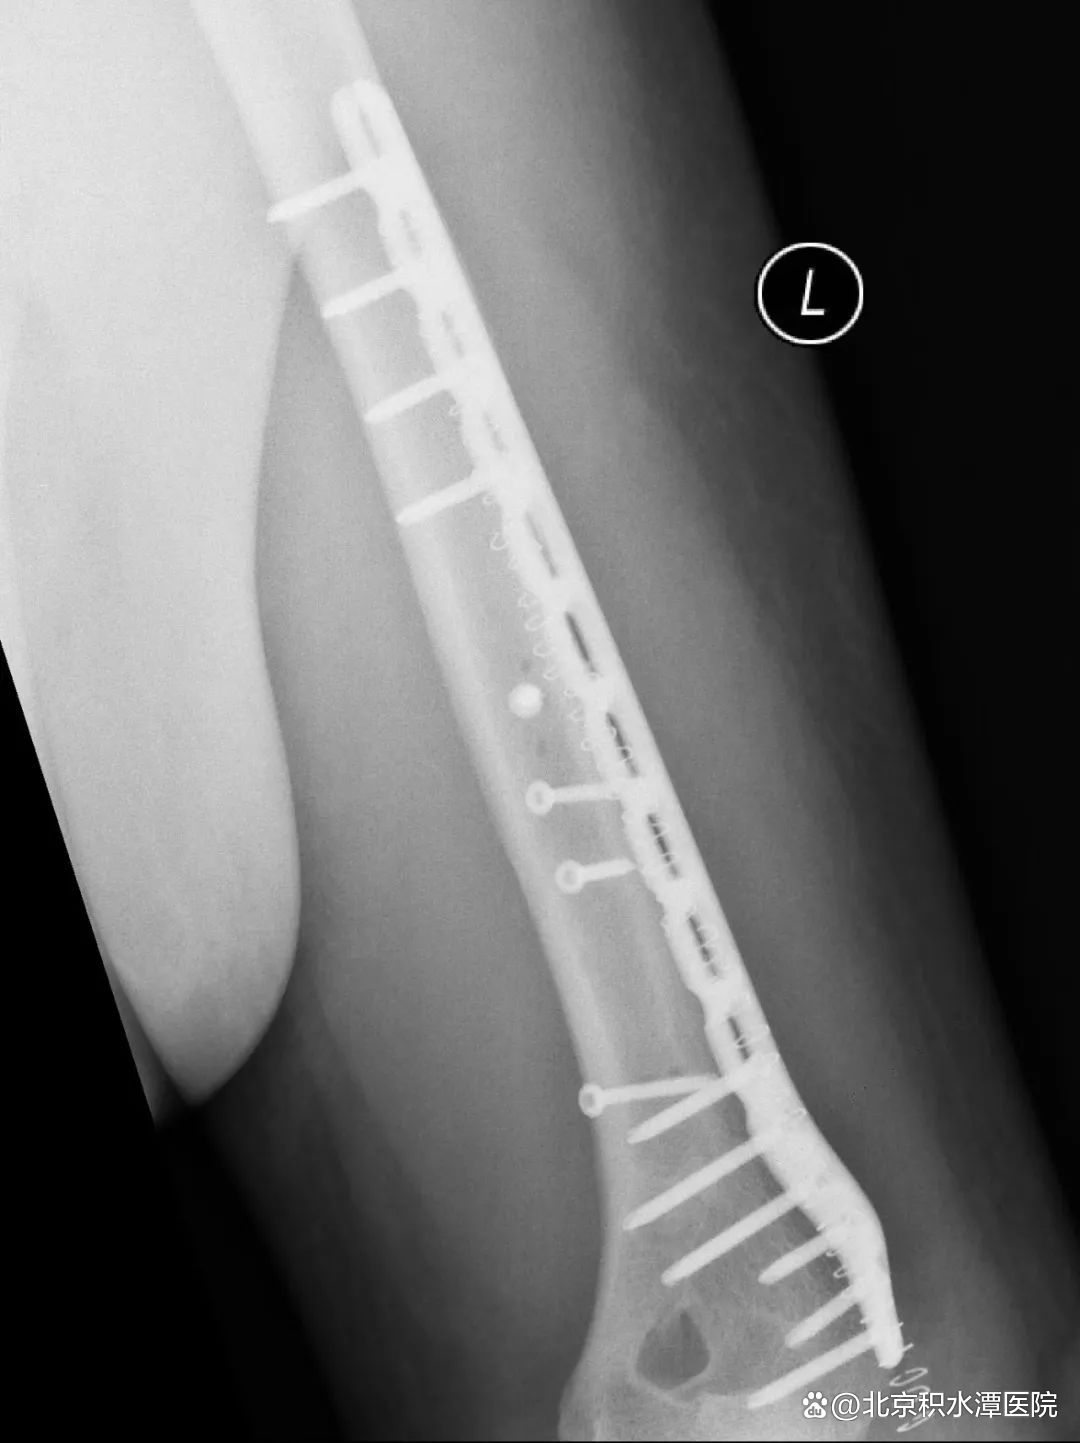

图|切开复位钢板螺钉内固定术

肱骨干骨折的治疗方法包括非手术治疗、闭合复位髓内钉内固定术和切开复位钢板螺钉内固定术等多种方式。采用非手术治疗时,可对患肢进行悬垂石膏固定或行闭合复位后使用上臂U型石膏固定,2-3周后解放肘关节,使用功能支具固定10-12周。由于扳手腕导致的肱骨干骨折几乎均为肱骨远端三分之一螺旋形骨折,闭合复位髓内钉内固定术不适合这类骨折,切开复位钢板螺钉内固定术是这类骨折的最佳的手术治疗方式